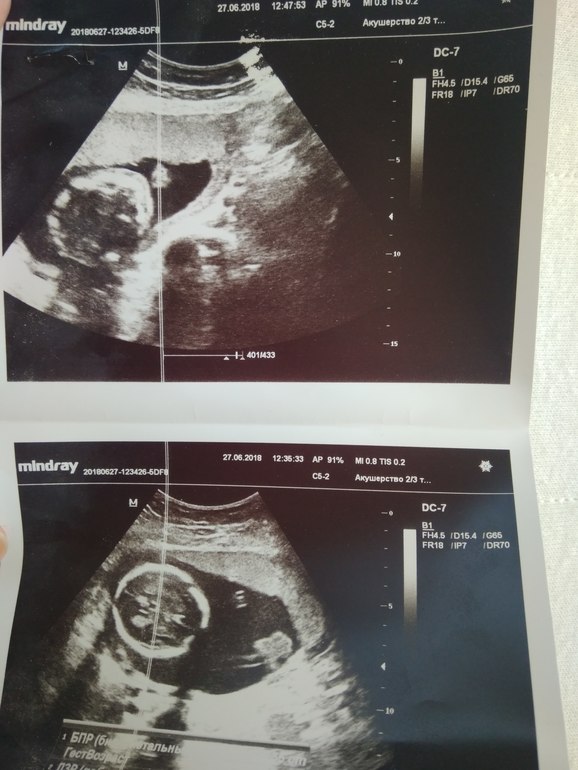

врач не знала что снять, потому голова одного в районе моего пупка и голова второго, в тазовом придлежании. Фото неинформативные вышли